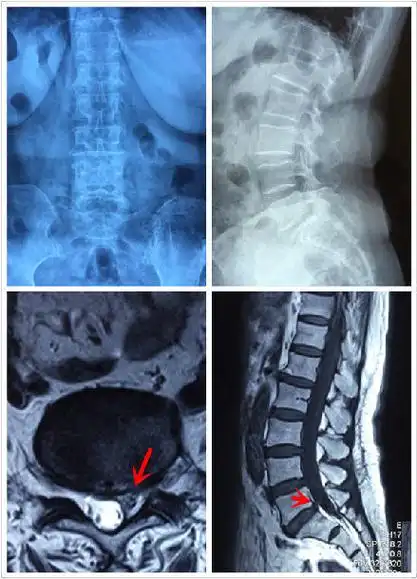

椎间孔镜微创治疗腰间盘突出(71岁女性,腰5-骶1)